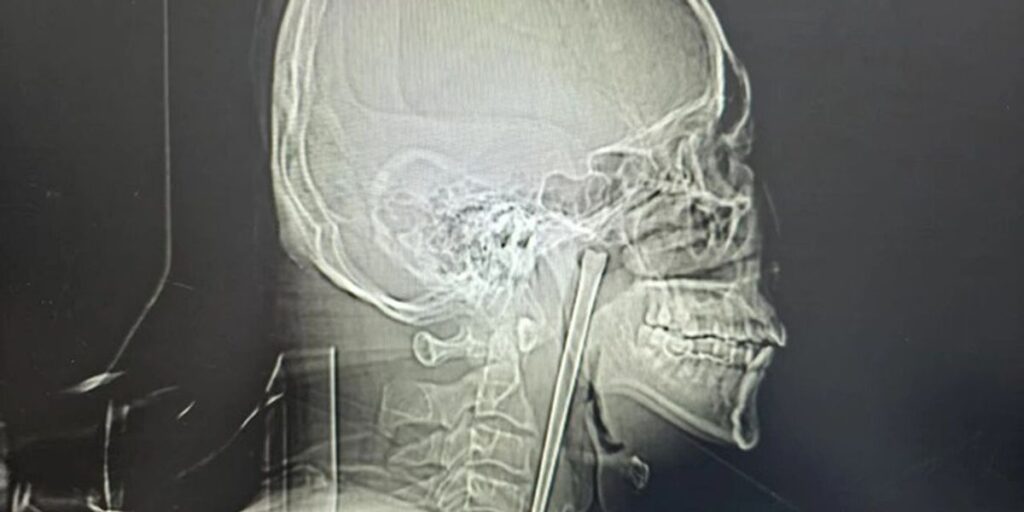

Shumica e njerëzve nuk do të mund të duronin as disa minuta me një shufër metalike 12-centimetërshe të bllokuar në fyt, por një burrë në Kinë arriti të jetonte kështu për plot tetë vjet, para se mjekët më në fund ta hiqnin me sukses.

Pas ekzaminimeve me rreze X, mjekët u habitën kur zbuluan një shufër rreth 12 centimetra të ngulur në fytin e pacientit. Kur e pyetën nëse e dinte për këtë, ai tha me qetësi se ishte një shkop metalik që e kishte gëlltitur aksidentalisht tetë vjet më parë, shkruan odditycentral.

Tetë vite më parë, Wang kishte gëlltitur aksidentalisht një chopstick metalik gjatë një vakti. Ai nuk tregoi saktësisht si ndodhi, por një raport nga spitali përmend se ai kishte pasur probleme me alkoolin. Edhe pse në fillim kishte ndjerë dhimbje dhe ndjesi mbytjeje në fyt, ai nuk kishte probleme me frymëmarrjen.